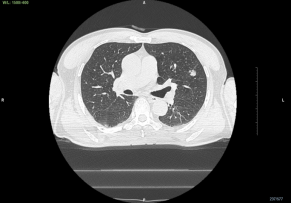

王大伯的病灶位于左肺上叶,直径约14mm。通过导航的引导,气管镜能到达结节所在的区域附近,但是并没有直接通向病灶的现成通路,最近的管腔距离肺结节还有2cm左右,如何透过气管管壁准确找到肺结节?

王大伯术前CT

术前规划/评估:病灶位置及最佳气道内路径